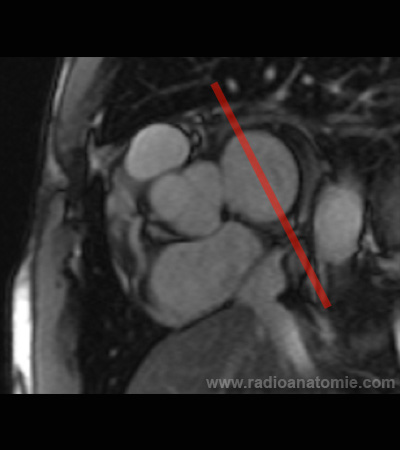

Radioanatomie et plans de coupe en IRM cardiaque

Plan chambre de chasse du ventricule gauche (LVOT)